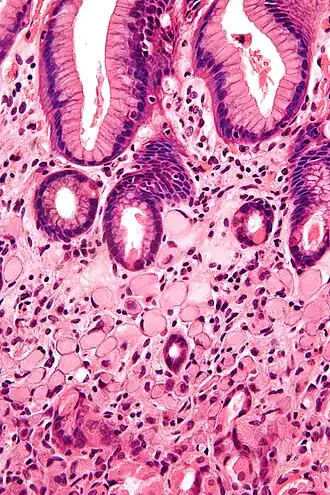

Histologia

O carcinoma de células escamosas surge da multiplicação descontrolada de células do epitélio e podem conter queratina e redes de filamentos ou desmossomos. Existem 6 sub-tipos: Adenoide, basaloide, células claras, células espinosas, células em anel de sinete e pleomórfico.